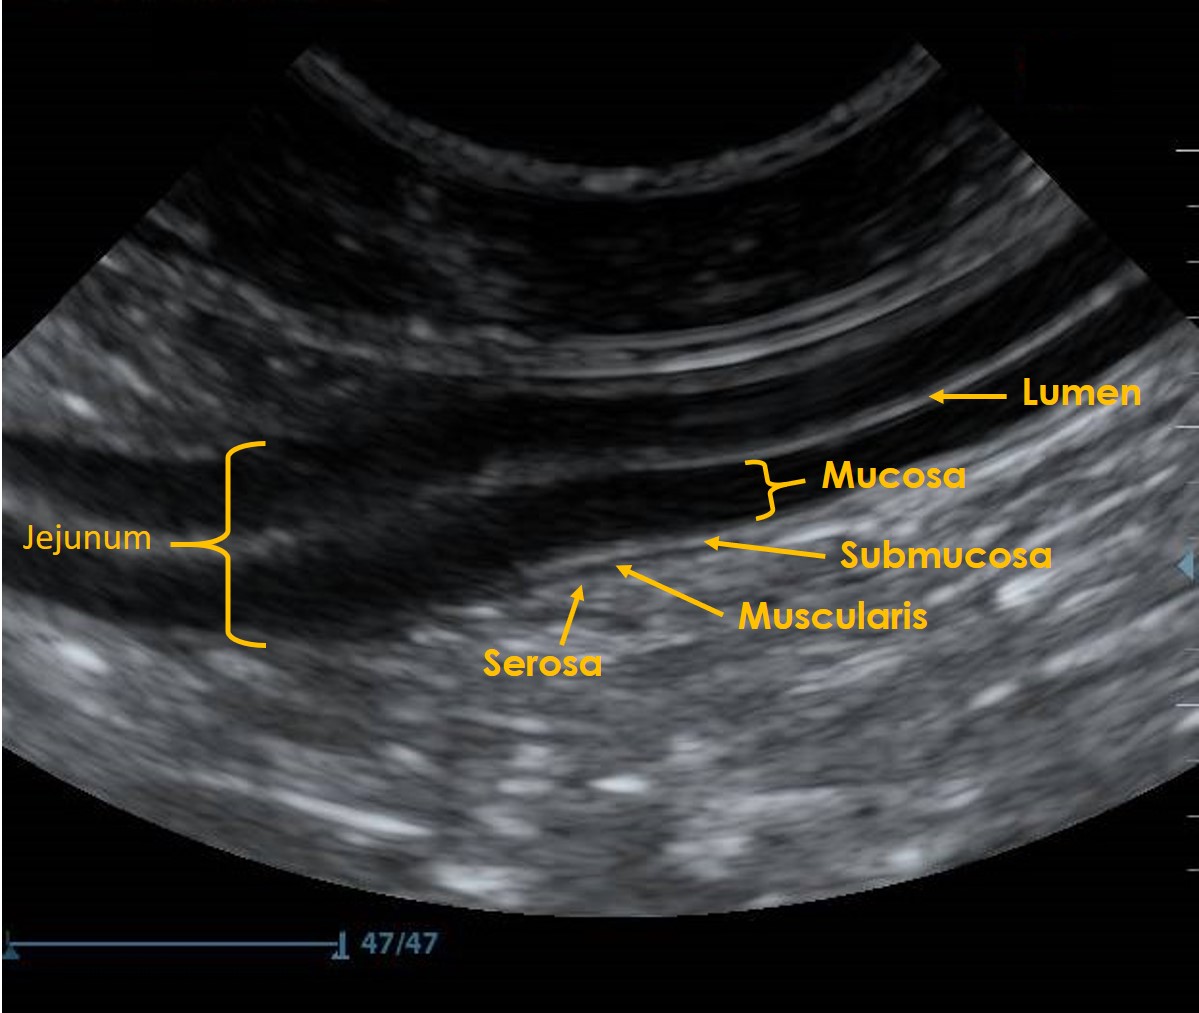

All sections of the GI tract share a common layered ultrasonographic appearance (Figure 2). However, the overall and relative thickness of parts of the GI tract layers varies with different sections of the GI tract.

Figure 2. A Jejunal loop imaged in longitudinal section – Wall layering of the gastrointestinal tract can be divided in to 5 distinct layers:

- Lumen – sometimes referred to as the luminal-mucosal interface. The lumen’s appearance can be variable depending on luminal contents, in this image the lumen is empty and exhibits a mucous pattern (hyperechoic line).

- Mucosa – hypoechoic in appearance, the width is variable dependent on the section of gastrointestinal tract.

- Submucosa – throughout much of the gastrointestinal tract this appears relatively narrow and hyperechoic.

- Muscularis – hypoechoic in appearance with variable thickness.

- Serosa – a thin hyperechoic layer, clear identification is often difficult.